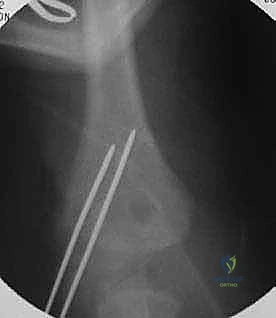

كسر اللقيمة الوحشية للعضد عند الأطفال هو إصابة شائعة في الكوع تتطلب رعاية متخصصة. يحدث غالبًا بعد السقوط، ويُعالج إما بالجبس للحالات البسيطة أو بالجراحة المفتوحة أو بالتثبيت بالأسلاك للحالات الأكثر تعقيدًا، بهدف استعادة وظيفة الكوع ومنع مضاعفات النمو.

الخلاصة الطبية السريعة والطارئة: يُعد كسر اللقيمة الوحشية للعضد (Lateral Condyle Fracture of the Humerus) عند الأطفال من أخطر إصابات الكوع وأكثرها دقة، كونه يمر مباشرة عبر "صفيحة النمو" المسؤولة عن استطالة العظم وتشكيله. يحدث الكسر غالباً نتيجة السقوط على يد ممدودة. العلاج يتراوح بين الجبس للحالات غير المتحركة تماماً (أقل من 2 ملم)، والتدخل الجراحي الدقيق (الرد المفتوح والتثبيت بالأسلاك) للحالات المتحركة. التأخير أو العلاج الخاطئ يؤدي إلى تشوهات دائمة في الذراع (اعوجاج الكوع) ومشاكل عصبية مستقبلية. في اليمن، يُعد الأستاذ الدكتور محمد هطيف المرجع الطبي الأول للتعامل مع هذه الحالات المعقدة بخبرة تتجاوز العقدين.

ثانياً: العلاج الجراحي (الرد المفتوح أو المغلق والتثبيت الداخلي)

الجراحة هي المعيار الذهبي والأكثر أماناً لأي كسر متحرك (أكثر من 2 ملم) أو الكسر الذي تعرض للدوران (Jakob Stage 2 & 3). الهدف من الجراحة هو إعادة القطعة المكسورة إلى مكانها بدقة ميكروسكوبية وتثبيتها بقوة لمنع حركة العضلات من إزاحتها مرة أخرى، مما يسمح للعظم بالالتئام السليم.

الخطوات التفصيلية للعملية الجراحية (الرد المفتوح والتثبيت الداخلي - ORIF)

بالنسبة للآباء، تعتبر فكرة خضوع طفلهم لعملية جراحية أمراً مرعباً. لكن فهم الخطوات الدقيقة للعملية يزيل الغموض ويبعث على الطمأنينة. يقوم الأستاذ الدكتور محمد هطيف بإجراء هذه العمليات بمهارة فائقة وتقنيات تحافظ على الأنسجة الرخوة.

1. التخدير والتحضير:

تُجرى العملية تحت التخدير العام لضمان عدم شعور الطفل بأي ألم ولضمان استرخاء العضلات تماماً. يتم تعقيم الذراع بالكامل وتغطيتها بمفارش جراحية معقمة. يتم استخدام جهاز الأشعة السينية المتحرك (C-arm) داخل غرفة العمليات.

2. الشق الجراحي (الوصول الآمن):

يُجري الجراح شقاً جراحياً صغيراً ودقيقاً (غالباً ما يكون تجميلياً) على الجانب الخارجي للكوع. الهدف هو الوصول إلى منطقة الكسر دون إتلاف الأعصاب أو الأوعية الدموية.